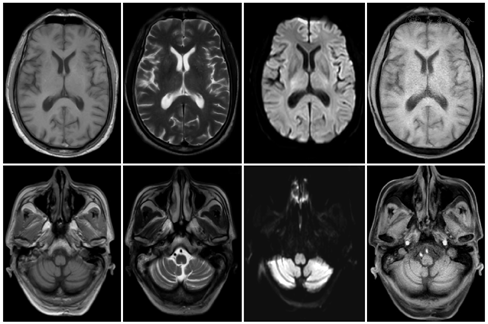

根据患者临床表现、体征及相关检查结果,诊断为并发于胃癌的抗Yo抗体阳性PCD,行胃癌根治术及肠粘连松解术,术后病理诊断:(全胃)腺癌,中-低分化,浸润至深肌层,未见脉管内癌栓。免疫组织化学检查结果:AE1/AE3(CK)(+),CK7(灶+),CK20(-),甲胎蛋白(-),肝细胞(-),癌胚抗原(+),胃Her-2(4B5)(3+),CD31(-),D2-40(-),Ki-67(约70%)(图4)。术后3个月随访患者,头晕、行走不稳、言语不清症状较术前稍好转,未完全缓解,因有消化系统基础疾病,仍存在食欲不佳。术后8个月随访,患者仍有言语不清,症状较术后3个月随访时无明显改善,头晕、行走不稳较前稍好转,能够独立行走,复查副肿瘤标志物检查:抗-Yo抗体仍为阳性。